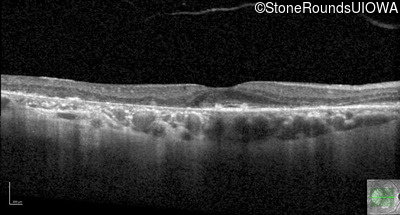

Optical Coherence Tomography - Right - 20/25 -2

Exemplar / OCT Stack